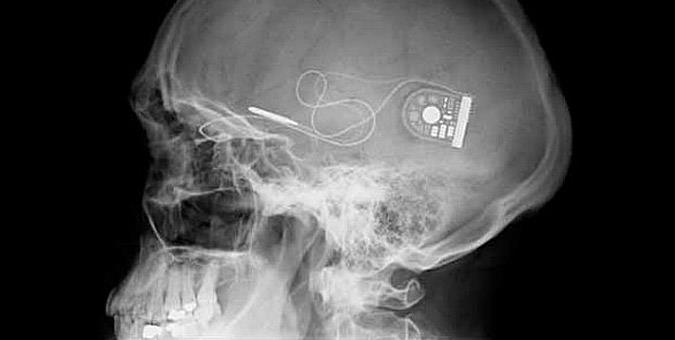

Άνθρωποι στο διάστημα, αόρατοι μανδύες, δυνατότητα όρασης σε τυφλούς. Η επιστήμη καλπάζει και κάνει πραγματικότητα την επιστημονική φαντασία. Δείτε 9 παραδείγματα.